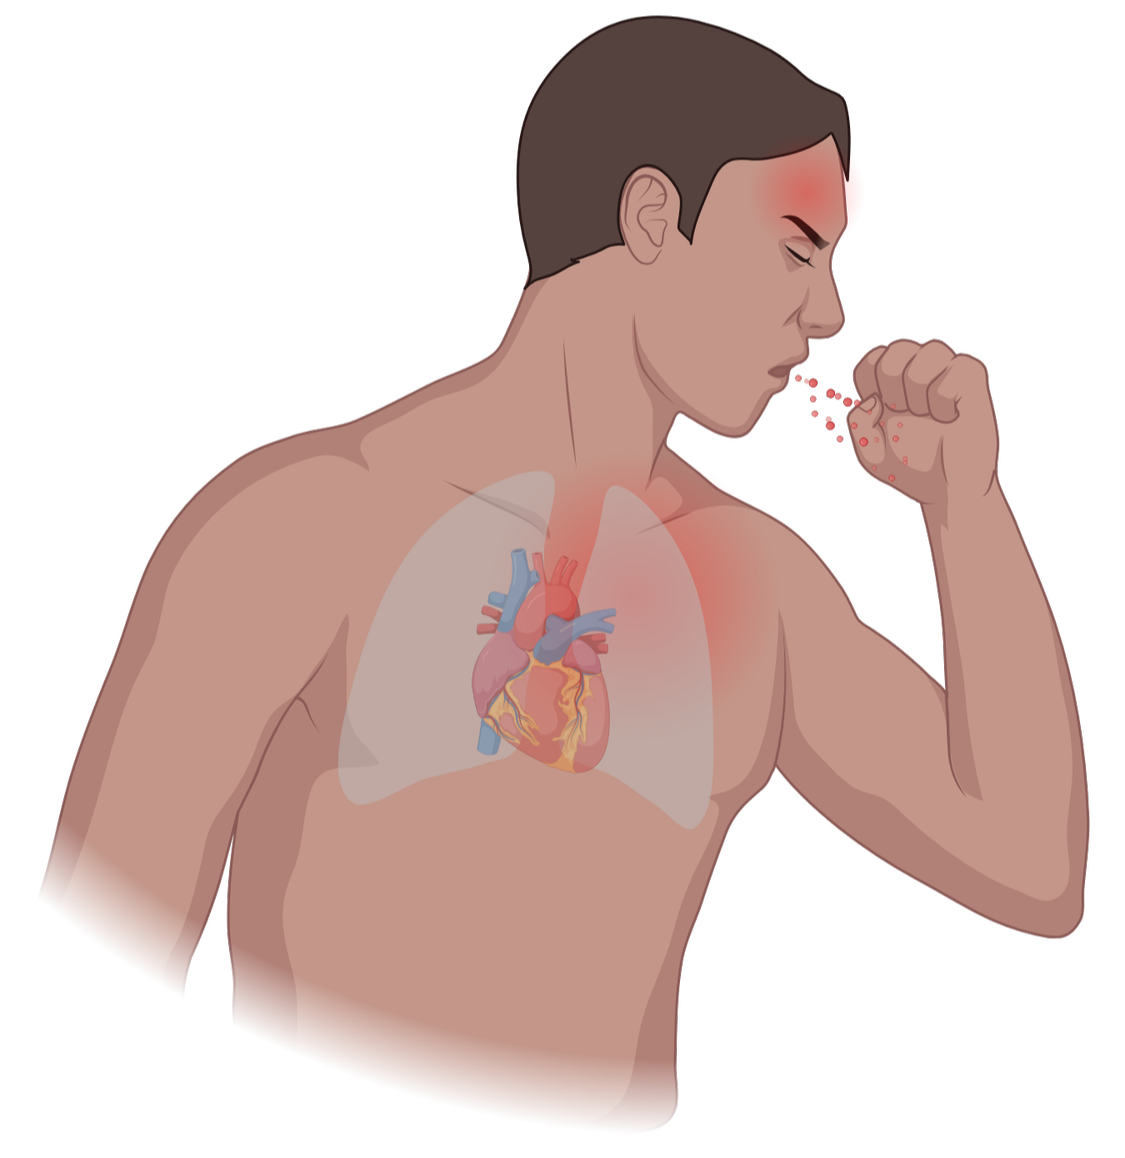

Un intrus nommé Willie vient de franchir votre peau. En quelques secondes, des milliards de soldats microscopiques se mobilisent : mangeurs voraces, espions futés, tireurs d’élite et tueurs à gages. Le champ de bataille ? Votre corps. Le prix ? Votre vie. Bienvenue dans la guerre silencieuse qui se déchaîne chaque fois que vous éternuez.